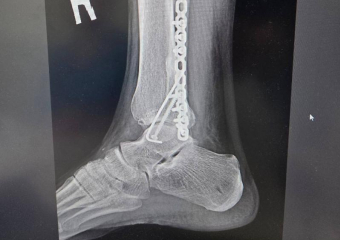

Дело закрыли: воронежец ищет свидетелей ДТП, в котором авто сломало ему ногу

За несколько месяцев правоохранители не смогли разобраться в обстоятельствах произошедшего В редакцию «Блокнота» обратился воронежец Сергей, ставший у...